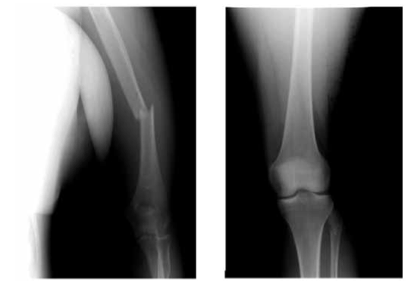

Больной Ж., 33 лет, доставлен в реанимационное отделение НИИ скорой помощи им. Н.В. Склифосовского через час после травмы - пешеход, сбит автомобилем. Осмотрен хирургом, нейрохирургом, травматологом. На основании клинической картины, рентгенографии груди, таза, нижних конечностей, УЗИ плевральных и брюшной полостей, КТ черепа и головного мозга установлен диагноз сочетанной травмы: ушиба головного мозга тяжелой степени, травматического субарахноидального кровоизлияния, разрыва правого крестцово-подвздошного сочленения, закрытого перелома правых подвздошной, лонной и бедренной костей, открытого перелома обеих костей правой голени, травматического шока II степени. При рентгенографии груди сразу после поступления правая половина диафрагмы несколько нечеткая за счет гидроторакса, расположена на уровне переднего отрезка VI ребра. Дренаж диаметром 20 Fr установлен в седьмом межреберье по средней подмышечной линии, эвакуировано 400 мл крови. После проведения интенсивной противошоковой терапии под эндотрахеальным наркозом выполнили стабилизацию переломов костей таза, бедра и голени аппаратами наружной фиксации и первичную хирургическую обработку раны голени.

Через 3 сут после травмы после стабилизации состояния и контрольной рентгенографии груди (рис. 1) пострадавший переведен на спонтанное дыхание и экстубирован, дренаж из правой плевральной полости удален. Рисунок 1. Рентгенограммы груди. а - 2-е сутки после травмы; б - 6-е сутки после травмы. Тяжесть состояния в этот момент определялась черепно-мозговой травмой и дыхательной недостаточностью I степени. При аускультации дыхание было ослаблено справа в базальном отделе. При рентгенографии на 6-е сутки после операции отмечены нечеткость контура и высокое расположение правой половины диафрагмы - на уровне переднего отрезка III ребра. При УЗИ подтверждено высокое расположение правой половины диафрагмы и обнаружен ее дефект с перемещением части печени в правую плевральную полость (рис. 2). Рисунок 2. Эхограмма правой плевральной полости на 6-е сутки после травмы. 1 - неповрежденный участок диафрагмы; 2 - печень, переместившаяся в правую плевральную полость через разрыв диафрагмы; 3 - жидкость в правой плевральной полости.

По стабилизации состояния пострадавший переведен в травматологическое отделение. Ему был последовательно выполнен внеочаговый остеосинтез правой бедренной и большеберцовой костей блокируемыми штифтами. В удовлетворительном состоянии выписан под наблюдение травматолога по месту жительства на 62-е сутки после травмы.